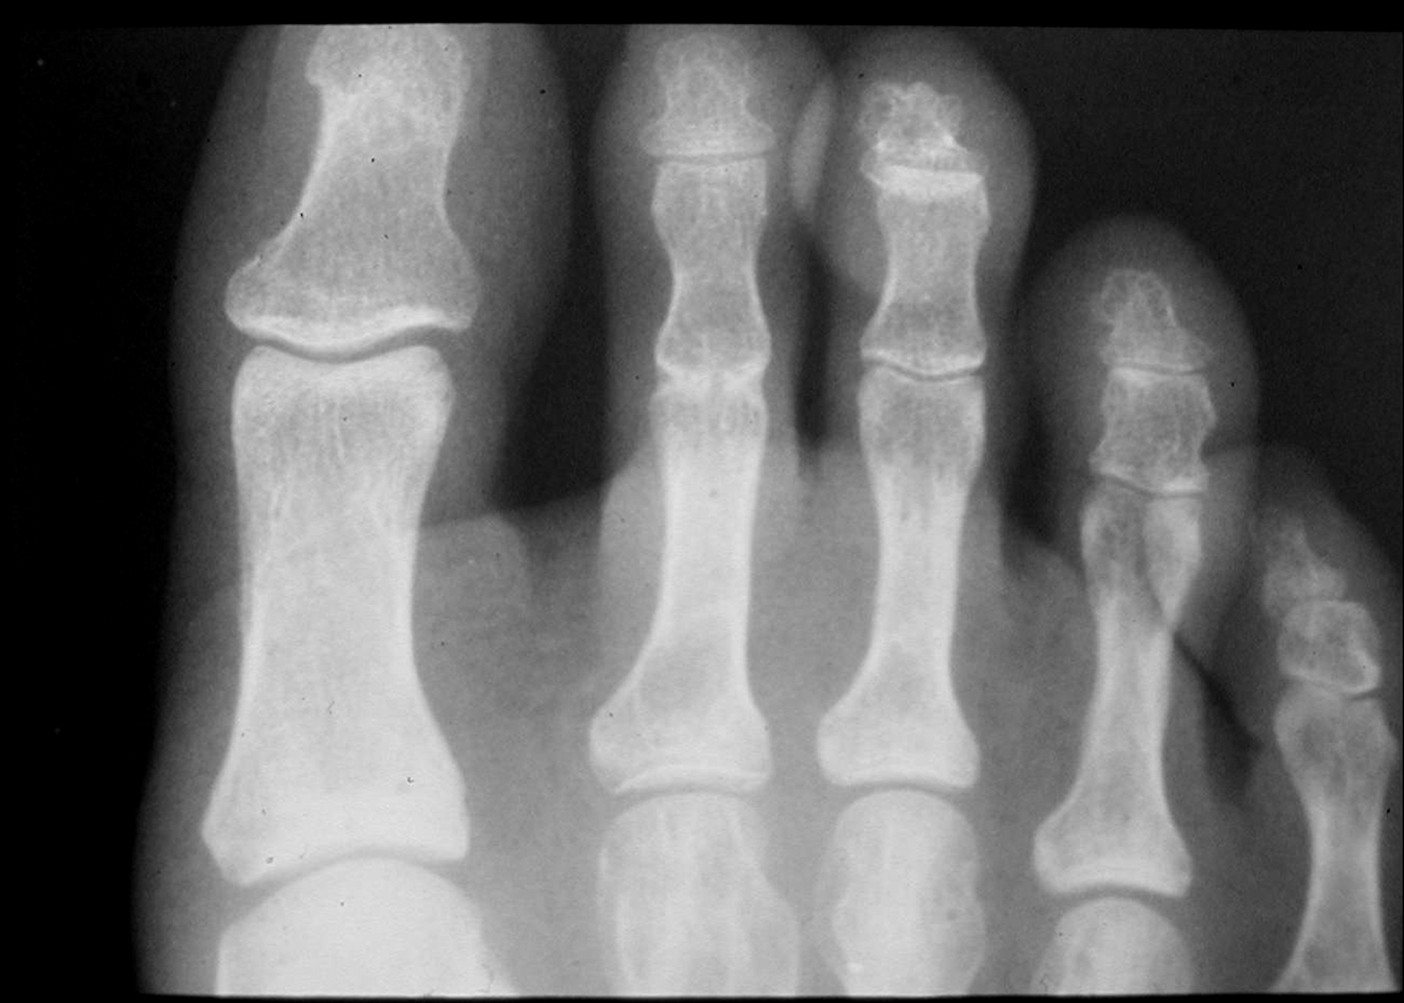

Such border conflicts are made possible by the lack of uniformity in the scope of podiatric practice from state to state. This, in turn, affects any number of issues from the education and training of podiatry residents to insurance regulations and billing once those residents graduate and start practicing. However, the ultimate losers might just be the patients who depend on DPMs for their foot care. Excessively limiting scope-of-practice laws drive a podiatrist like Michelle Butterworth, DPM, up the proverbial wall. She is the President of the South Carolina Podiatric Medicine Association and a tireless combatant in the scope wars between South Carolina podiatrists and their opponents in orthopedics and other fields. “South Carolina is one of the most restrictive states in the nation,” she notes from her clinic in Kingstree, S.C. “We cannot perform ankle surgery nor can we perform multiple digital amputations, according to our state law.” The reasons behind the limited scope simply do not add up to Dr. Butterworth. “An amputation is technically not that difficult to do compared to some of the other reconstructive surgeries we do,” she says. “It is a little frustrating that we cannot do something relatively simple like an amputation but we are able to do a major foot reconstruction. It does not make sense.” Dr. Butterworth has seen her share of political wrangling in the South Carolina state government over scope of practice, coming tantalizingly close in 2006 to broadening allowable procedures for podiatrists. “The bill we submitted last year would have allowed us to do both partial foot amputations and ankle surgery,” she explains. “It actually got approved in the state House but was defeated by the Senate. Unfortunately, our bill and all of our hard work were defeated by a Senate subcommittee of only three people.” While Dr. Butterworth vows to submit the same bill in the current legislative session with the hope of success this time out, she understands only too well the political obstacles in her way and how the mathematics of representation do not favor her cause. “Unfortunately, with our laws as restrictive as they are, a lot of podiatrists do not want to practice in South Carolina because they cannot do everything they have been trained to do,” she admits. “South Carolina does not have a lot of podiatrists. We do not have a big membership and when you do not have a big membership, you do not have a lot of money to spend on legislative activities to have a louder voice in policy discussions. As everyone knows, politics and money go hand in hand, and when you do not have the bucks to spend on lobbyists and things to promote your cause, it makes it very difficult.”

Another state that has seen its share of podiatry-related legislative fights is Texas. Most notably, in August 2005, the 345th Texas Judicial District Court upheld the opinion of the Texas State Board of Podiatric Medical Examiners, including the ankle in the definition of the “foot” used by medical practitioners. That definition was contested by the Texas Orthopedic Association and the Texas Medical Association, which argued that podiatric treatment should be confined to the foot and not to the ankle or anywhere else in the anatomy. Appellate and legislative skirmishes resulting from this decision occur to this day. One of those affected by the decision (and most vocal about the importance of a broader definition of podiatric care) is Richard Pollak, DPM, who is based in San Antonio. Dr. Pollak has heard all the opposing voices in the fray but says podiatrists have the upper hand — for now. “We have the law on our side,” he explains. “The law in Texas states that we as podiatrists can perform surgery on the ankle. The foot and ankle orthopedists’ position is, ‘What happens if we are successful in our lawsuit and we reverse that law? Then we have to de-credential you. That will not look good on your credentials when you apply to various hospitals.’” Such a threat makes little sense to Dr. Pollak and neither does the reasoning behind his opponents’ position. “They claim there is not adequate training for podiatrists to handle foot operations,” he notes. “Another reason is that podiatrists cannot handle any complications, meaning if one had a problem with an ankle arthrodesis and the ankle became infected and the infection went up the leg, the podiatrist cannot go up the leg and do a below-the-knee amputation. That is one of their big arguments, namely that we cannot handle the complications if the complications go superior, if you will, to the location of the ankle.” Dr. Pollak compares the situation to abortion laws. If abortion is ever outlawed, he says doctors who performed abortions while they were legal would not face legal or professional consequences. “If an orthopedist did a total hip procedure and he cuts the femoral artery and is not able to stop it from bleeding, he might call in a vascular surgeon,” he continues. “If a podiatrist does an Achilles tendon lengthening and somehow there is a mistake—say it tears further up above the level of the ankle—is the podiatrist equipped to go above the level of the ankle? The answer, once again, is that you call in someone else, a foot and ankle orthopedist, for example. “Then their response to that is: ‘We do not want to be around just to handle all your junk, your complications.’ I think that is a poor argument.” In South Carolina, podiatrists practice within a restricted scope but they are fighting through legislation to expand that scope. In Texas, they practice under an expanded scope that includes the ankle but are beset with legal challenges. In other parts of the country, podiatrists must fend off similar legal disputes and legislative encroachments. In 2006, Florida — with its plethora of medical colleges — was the battleground for a skirmish over state House Bill 575, which sought to amend the definition of “practice of podiatric medicine” from its current scope (extending to the tibial tubercle) to a more restricted area (stopping at the ankle). The bill would have also limited optional Medicaid services reimbursements for certain podiatric procedures. The efforts of the Florida Podiatric Medical Association and other DPMs in the area were reportedly crucial in the defeat of the bill, which died in committee.